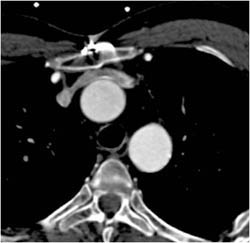

CCTA: LAD Disease